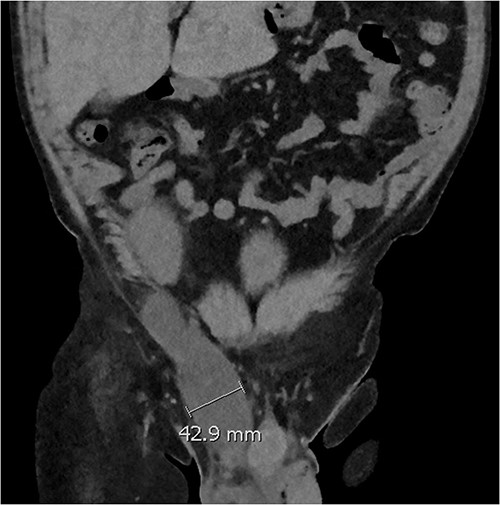

Five days later, the patient had another ultrasound and an ensuing CT KUB given recurrence of a painful groin swelling overnight. It showed a reaccumulation of the pelvic fluid collection, which extended into the groin toward the scrotum with two pockets of fluid collection measuring 4.6 × 6.5 × 2.7 cm (42 ml) and 7.7 × 3.5 × 4.6 cm (66 ml) (Figs 2 and 3). We temporized the situation by aspirating 35 ml of fluid by the bedside under ultrasound guidance for symptom relief and booked him for an elective operation given the complex anatomy of the collection.

Coronal CT scan showing lobulated low-density fluid collection adjacent to the lower pole of the transplant kidney in the right iliac fossa and extending into the superficial inguinal canal tracking along the inguinal and scrotal hernia with a maximal width of 43 mm in transverse diameter.